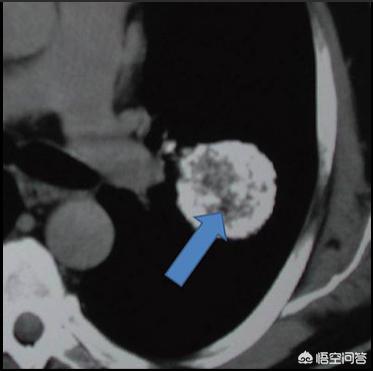

首先要明确一点,我们称做肺癌的,都是恶性肿瘤,没有良性肺癌这一说法,肺上的良性肿瘤都有其他的名字,如硬化性血管瘤、腺瘤、脂肪瘤、错构瘤等。对于良性的肿瘤,一般都是可以治疗的;而对于恶性的肺癌,早期肺癌治疗效果是不错的,晚期肺癌相对来说预后要差很多。

总结:肺内肿瘤有良恶性之分,但是没有良性肺癌的说法,肺癌都是恶性的,所以如果发现肺内占位,建议及时弄清楚良恶性,及时选择正确的治疗方法。